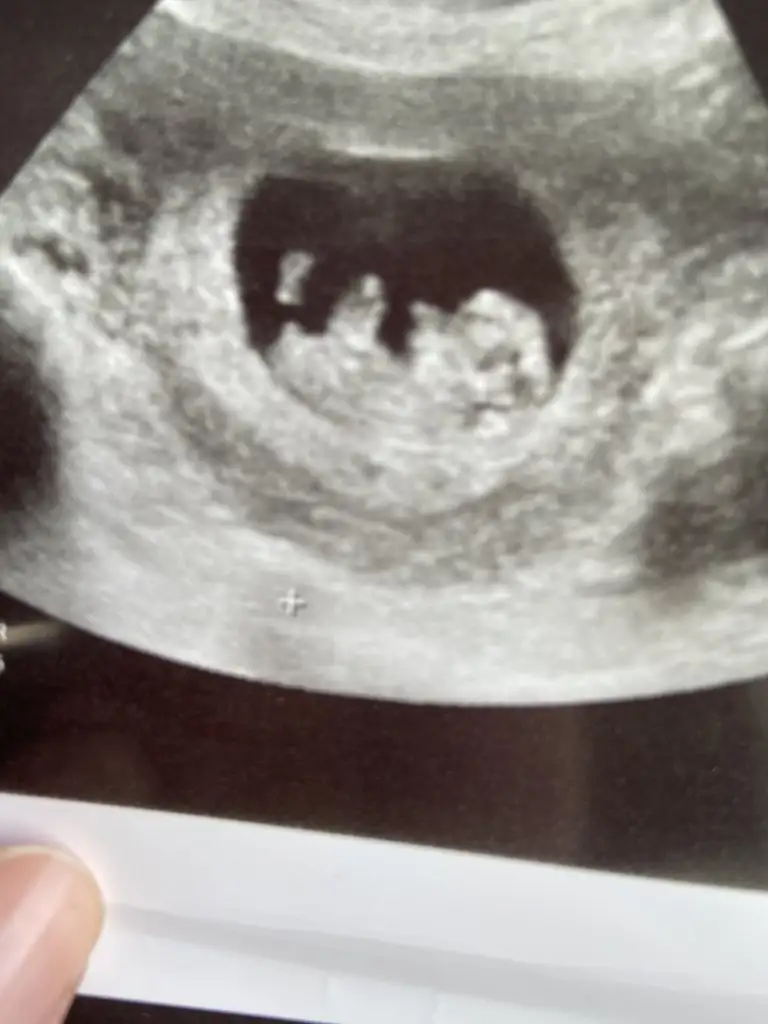

Merhaba 6 haftalik hamileyim benim karından ultrason sonucuna da bakarmisinizMerhaba, kız gibi görünüyor. Sağlıkla gelsin inşallah

Merhaba bence kız. Saglıkla gelsin de yeterMerhaba 6 haftalik hamileyim benim karından ultrason sonucuna da bakarmisiniz

Erkek gibi canım bence6+1 haftalık görüntü cevap verebilecek olan var mıdır?karından ultrason